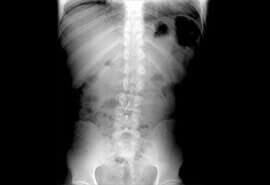

En el consultorio del Dr. Juan Fco. López Garza usted cuenta con la asistencia de un médico reumatólogo en Tampico, Tamaulipas especialista en el tratamiento de artritis reumatoide, tratamiento de osteoporosis y tratamiento de dolor de lumbalgia, así como para otros múltiples padecimientos.

está capacitado para diagnosticar a sus pacientes, dar seguimiento y control adecuado al problema que le causa una deficiencia en su sistema óseo en busca de eliminar el dolor de huesos y malestares que estos conllevan.

tratamiento de artritis reumatoide y atención especializada en reumatología es empleada tecnología de punta y los tratamientos más eficaces para disminuir dolencias y síntomas, de esta forma usted tendrá una mejor calidad de vida.